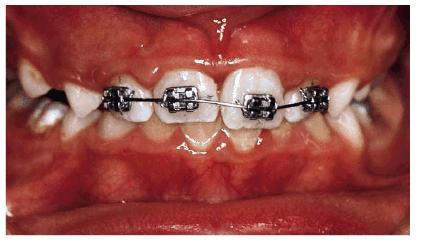

A male patient, 8 years, 3 months old.

PROBLEM: The patient presented with a complicated enamel-dentin fracture

of the left central incisor with an immature apex. The patient had poor oral

hygiene and a class II molar relationship. The tooth fragment was available,

although it was not complete (Figures 27-7A

and B

Figure 27-7A and B: A complicated enamel-dentin fracture of tooth 9 and the radiograph.

TREATMENT: After cleansing and stopping the flow of blood, the restoration was done in accordance with standard procedures. After pulp capping with calcium hydroxide, the tooth fragment was reattached. However, because the fragment was not complete, the missing parts were reconstructed with composite resin, and the entire periphery of the fractured surface of the remaining tooth was beveled to improve esthetics (Figure 27-7C

Figure 27-7C: The tooth fragment is reattached with a bevel to improve esthetics.

RESULT: Immediately after restorative treatment, the patient expressed

his satisfaction. After 18 months, the patient returned, reporting an extrusive

luxation of tooth 9 following a school incident. The tooth was immediately

repositioned and splinted orthodontically (Figure 27-7D). A. 018 nytinol wire was used for

15 days. It was subsequently removed after clinical and radiographic

confirmation of results.

Figure 27-7D: After 18 months, the same tooth has an extrusive luxation and is orthodontically splinted.

The patient had periodic radiographic examinations and sensitivity tests to

monitor pulp and root healing, as well as tooth vitality (Figure 27-7E).

Figure 27-7E: The radiograph after the reposition.

From an orthodontic perspective, a serious skeletal Class II with deep bite is becoming more and more evident. Therefore, orthodontic treatment has been initiated in both arches to align the dentition over the basal bone in harmony with the surrounding hard and soft tissues, as well as to achieve good esthetics (Figures 27-7F and G

Figure 27-7F and G: The same patient during the orthodontic treatment and after. Good esthetics has been achieved.